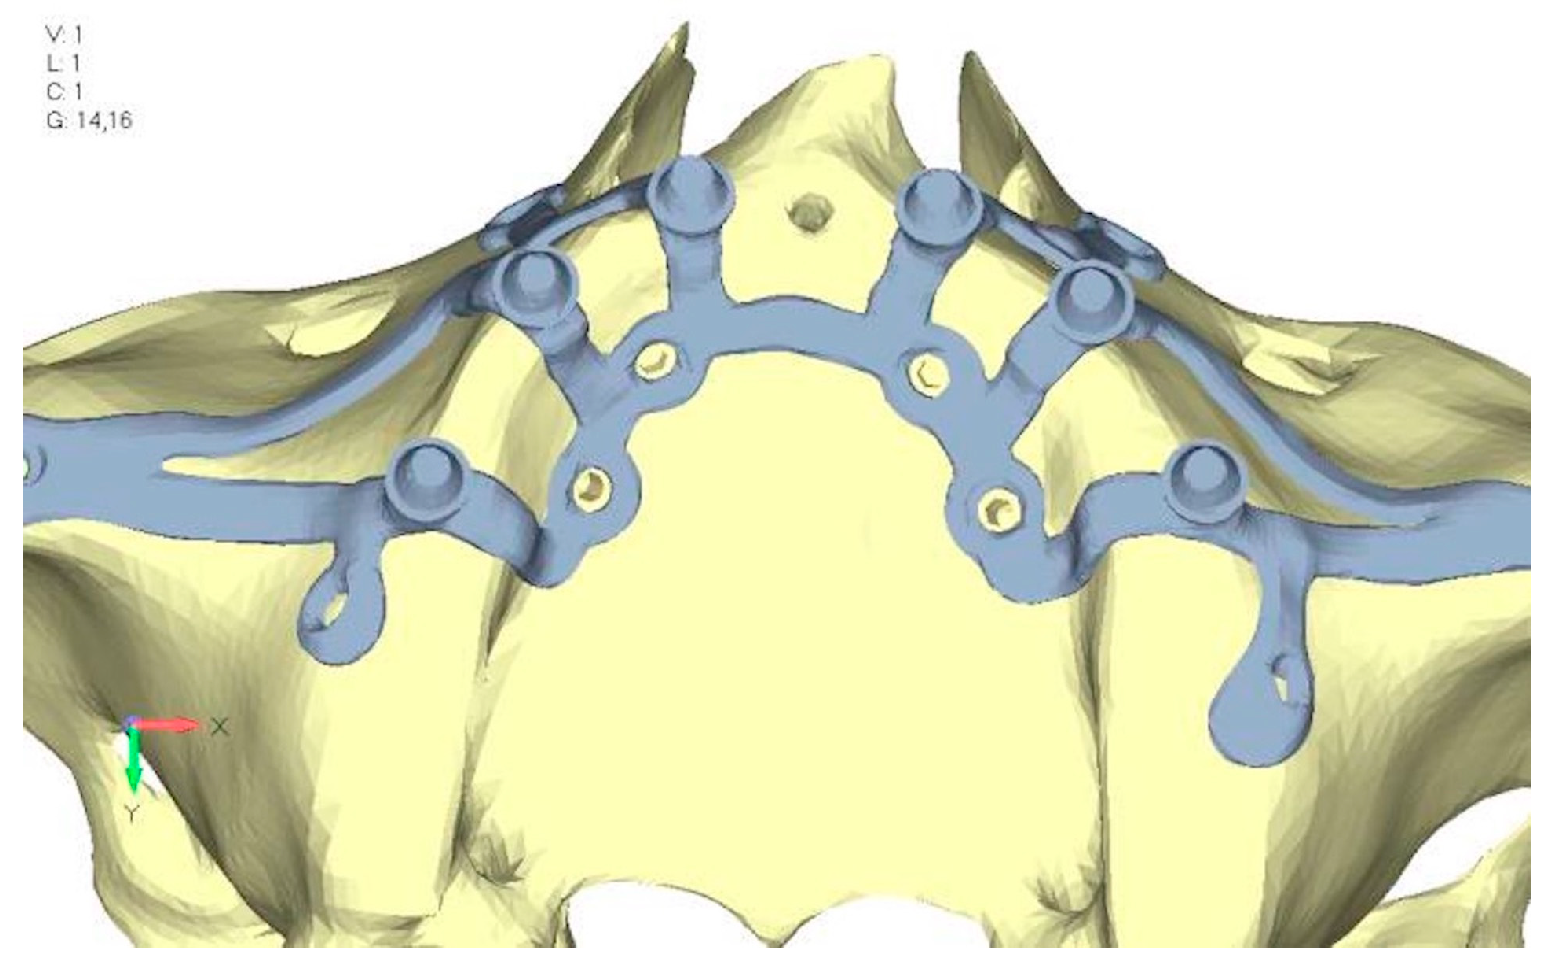

- Model V2. This model serves as an alternative to model V1, as it aims to stabilize the structure posteriorly using screws placed in the vestibular direction rather than the palatal direction (Figure 10). The model displayed similar behavior to V1, leading to the decision to proceed with V1 for further development (Figure 11a,b).